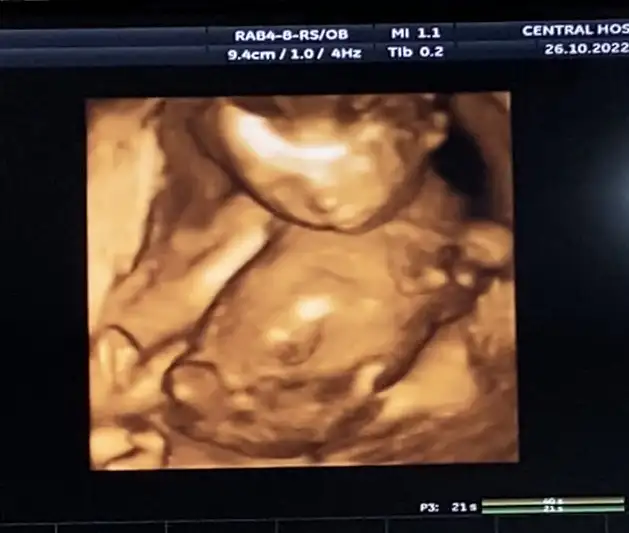

fiziksel kısıtlamaya git , mümkün mertebe kalkma, eğilme, yerden bir şey almaya kalkma ,yukarı uzanma ki karın iç basıncın değişikliğe uğramasın. 1 hafta içindeki değişimi gözlemleyecektir. inşallah bi şey çıkmaz. rahim ağzı geri toparlayabiliyormuş çünkü.

bende 2 haftada bir gidiyorum şu an önlem olarak.